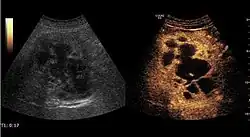

Encephaloid hepatocellular carcinoma (CEUS). Contrast tumor enhancement is observed on the left during arterial phase. The “wash-out” phenomenon can be seen on the right, during portal venous phase.

HCC appearance on 2D ultrasound is that of a solid tumor, with imprecise delineation, with heterogeneous structure, uni- or multilocular (encephaloid form). An "infiltrative" type is also described which is difficult to discriminate from liver nodular reconstruction in cirrhosis. Typically HCC invades liver vessels, primarily the portal veins but also the hepatic veins . Doppler examination detects a high speed arterial flow and low impedance index (correlated with described changes in tumor angiogenesis). The spatial distribution of the vessels is irregular, disordered. CEUS examination shows hyperenhancement of the lesion during the arterial phase. During the portal venous phase there is a specific "wash out" of ultrasound contrast agent (UCA) and the tumor appears hypoechoic during the late phase. Poorly differentiated tumors may have a stronger wash out leading to an isoechoic appearance to the liver parenchyma during portal venous phase. This appearance was found in approx. 30% of cases. The described changes have diagnostic value in liver nodules larger than 2 cm.